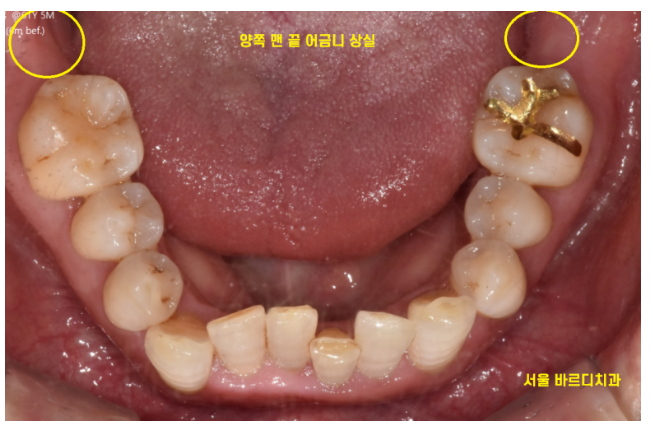

하남시청치과 처음 방문해주셨을 때

왼쪽, 오른쪽 맨 아래 끝에 어금니가

각각 1개씩 상실한 채로 오셨습니다.

하남시청치과 임플란트 그 결과는,,?

231229

원하는 위치에 각도가 예술로 정확히 들어갔습니다.